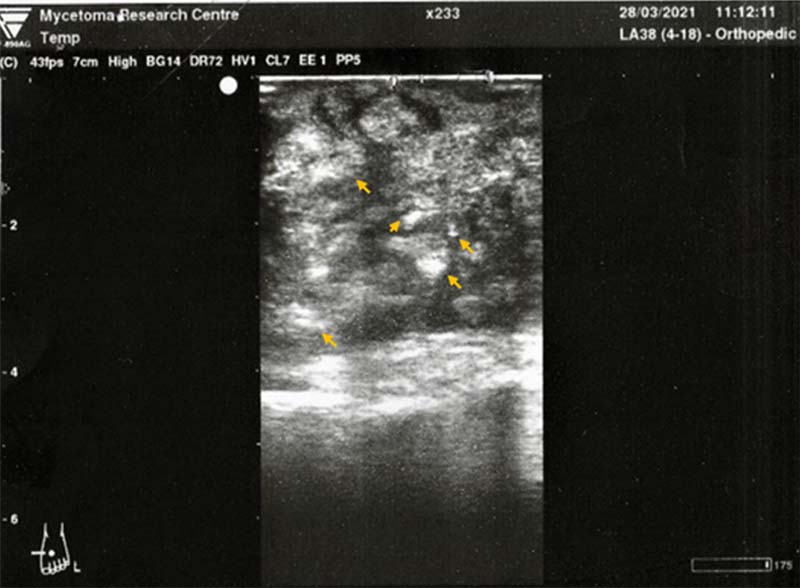

Ultrasonic Imaging of Mycetoma

The mycetoma grains, capsule, and the accompanying inflammatory granuloma have characteristic ultrasonic appearances. Ultrasound imaging can differentiate between eumycetoma, actinomycetoma, mycetoma and other non-mycetoma lesions. The grains produce numerous sharp, bright hyperreflective echoes consistent with the black grains in eumycetoma lesions. The grain cement substance is most probably the origin of these sharp echoes. Also, there are multiple thick-walled cavities with absent acoustic enhancement. In actinomycetoma lesions, the findings are similar, but the grains are less distinct. This may be due to their smaller size and consistency, the individual embedding of the grains or the absence of the cement substances in a few.

The ultrasonic diagnosis of mycetoma is more precise and accurate in lesions with no sinuses. The size and extent of the lesion can be accurately determined ultrasonically, which is useful in planning surgical incisions and procedures.